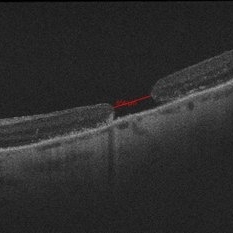

Macular Hole

Macular Hole

Jul 1 2014 by John S. King, MD

High myope c history of mac-off rrd c inf tear and ftmh that appeared chronic on presentation. RD repaired, hole remained open. ILMx performed with inverted flap. One month post MHx.

Photographer: Wayne A Ladlee Jr

Imaging device: Cirrus

Condition/keywords: macular hole, myopic degeneration

Macular Hole

Macular Hole

Jul 1 2014 by John S. King, MD

High myope c history of mac-off rrd c inf tear and ftmh that appeared chronic on presentation, RD repaired, hole remained open.

Photographer: Wayne A Ladlee Jr

Imaging device: Cirrus

Condition/keywords: macular hole, myopic degeneration

Macular Hole

Macular Hole

Jul 1 2014 by John S. King, MD

High myope c history of mac-off rrd c inf tear and ftmh that appeared chronic on presentation. RD repaired, hole remained open. ILMx performed with inverted flap. One and three months s/p MHx.

Photographer: Wayne A Ladlee Jr

Imaging device: Cirrus

Condition/keywords: macular hole, myopic degeneration